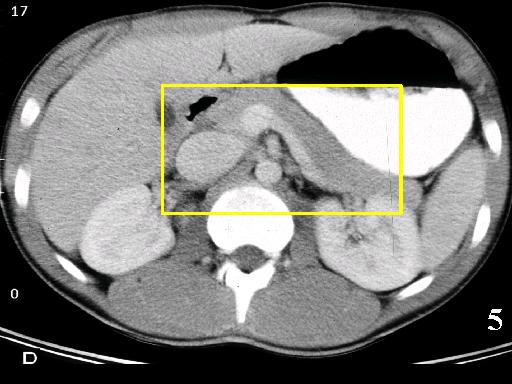

MS 190 CT 16